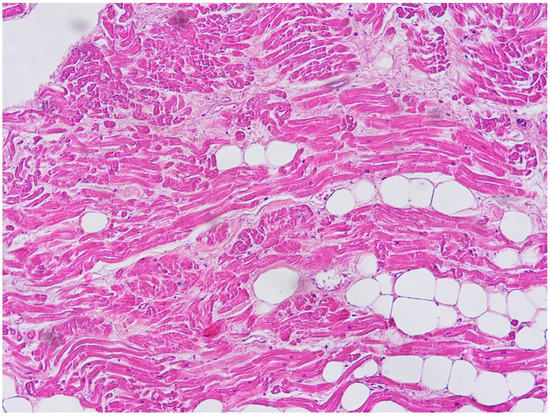

2. Case Report

6.1. Autopsy Findings